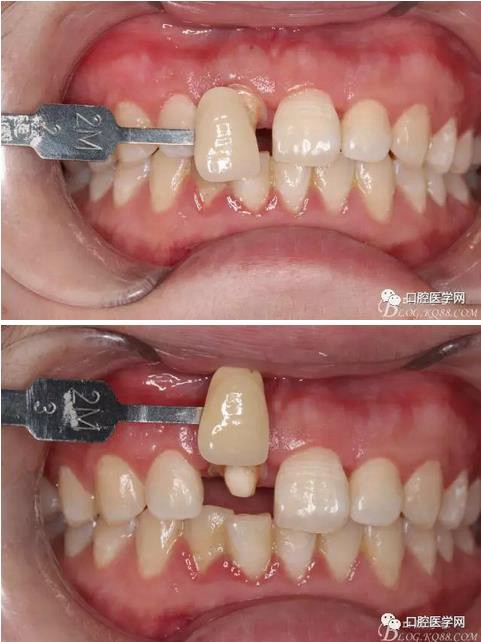

牙冠延長(zhǎng)術(shù)后6周復(fù)診牙齦齦緣形態(tài)恢復(fù)良好,齦乳頭有些欠缺,患者著急永久修復(fù)。

比色